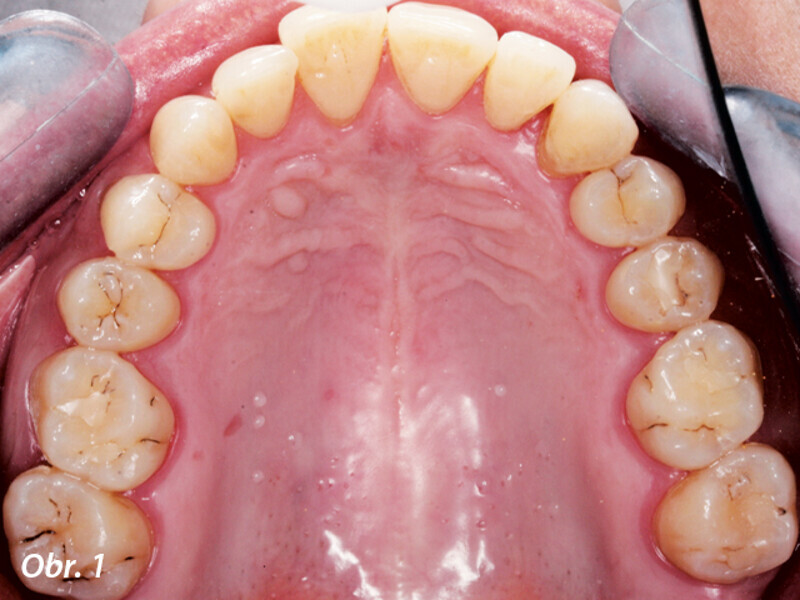

Funkční, anatomická a estetická harmonie s novým kompozitním materiálem Enamel Plus HRi